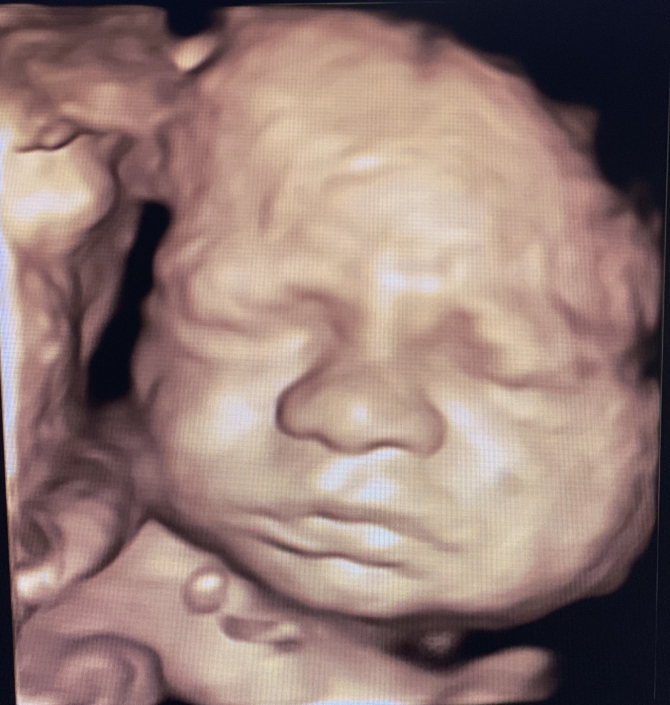

Prenatal Peek®

Prenatal Peek is the leader in 3D 4D Ultrasound. We employ only Certified / Registered Sonographers maintaining unsurpassed standards in 3D ultrasound. You deserve the best! Call us today.